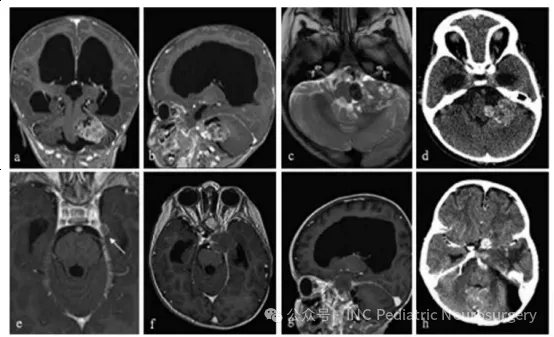

患者于2015年就诊,14个月大,主诉为巨头畸形(macrocephaly)2个月、中央性肌张力低下、声音微弱、吞咽困难,以及发育倒退。检查发现显著交通性脑积水与巨脑症,并伴有左侧小脑桥脑角(CPA)巨大异质性强化病灶,影像学可见出血伪影(blooming artifact)、液-液平面(fluid-fluid levels),且肿瘤压迫脑干(图6)。

患者接受左侧后乙状窦开颅术(retrosigmoid craniectomy)。术中冰冻病理提示淋巴样细胞,仅能行次全切除(subtotal resection),脑干部位仍有肿瘤残留。术后,患者持续存在颅神经功能缺损、吞咽困难(需行胃造口术),以及原因不明的交通性脑积水(需行脑室-腹腔分流术)。

最终石蜡病理结果显示为非典型脊索瘤(atypical chordoma),免疫组化Brachyury、pan-CK、EMA、IN11基因产物(BAF47/IN11)均为阳性。在已报道的儿童脊索瘤病例中,该患者是年龄最小的病例之一,也是唯一发生在CPA区域的病例。

由于患儿年龄极小、肿瘤位置特殊且病理类型为非典型,治疗决策由多学科团队(MDT)制定。她接受了3个周期ICE方案化疗。虽然术后临床情况相对稳定,但随访影像显示手术部位病灶进展,同时在左侧颞叶凸面出现新的硬膜基底结节性强化灶,考虑可能为脑膜播散。

此时,患者接受3个月常规放疗,并对左侧CPA区域实施伽马刀强化照射。遗憾的是,肿瘤在放疗期间继续进展,MRI显示肿瘤向侧方侵入Meckel腔,并向左小脑幕后方延伸。

全外显子测序显示SMARCA4突变,随后开始Vorinostat+顺-维甲酸(cis-retinoic acid)化疗。尽管采取了积极治疗,肿瘤仍快速进展,累及左侧海绵窦、眶区及颅中窝。患者在短期姑息治疗后去世,距首次诊断约1年。

图6. 患者10左桥小脑角区脊索瘤影像学随访资料

(a)术前轴位T1加权钆增强MRI;

(b)术前矢状位T1加权钆增强MRI;

(c)术前轴位T2加权MRI;

(d)术前轴位CT扫描;

(e)术后5个月轴位T1加权钆增强MRI,显示左颞部新发硬膜病变(箭头);

(f)术后9个月轴位T1加权钆增强MRI;

(g)术后9个月矢状位T1加权钆增强MRI;

(h)术后12个月轴位CT扫描。